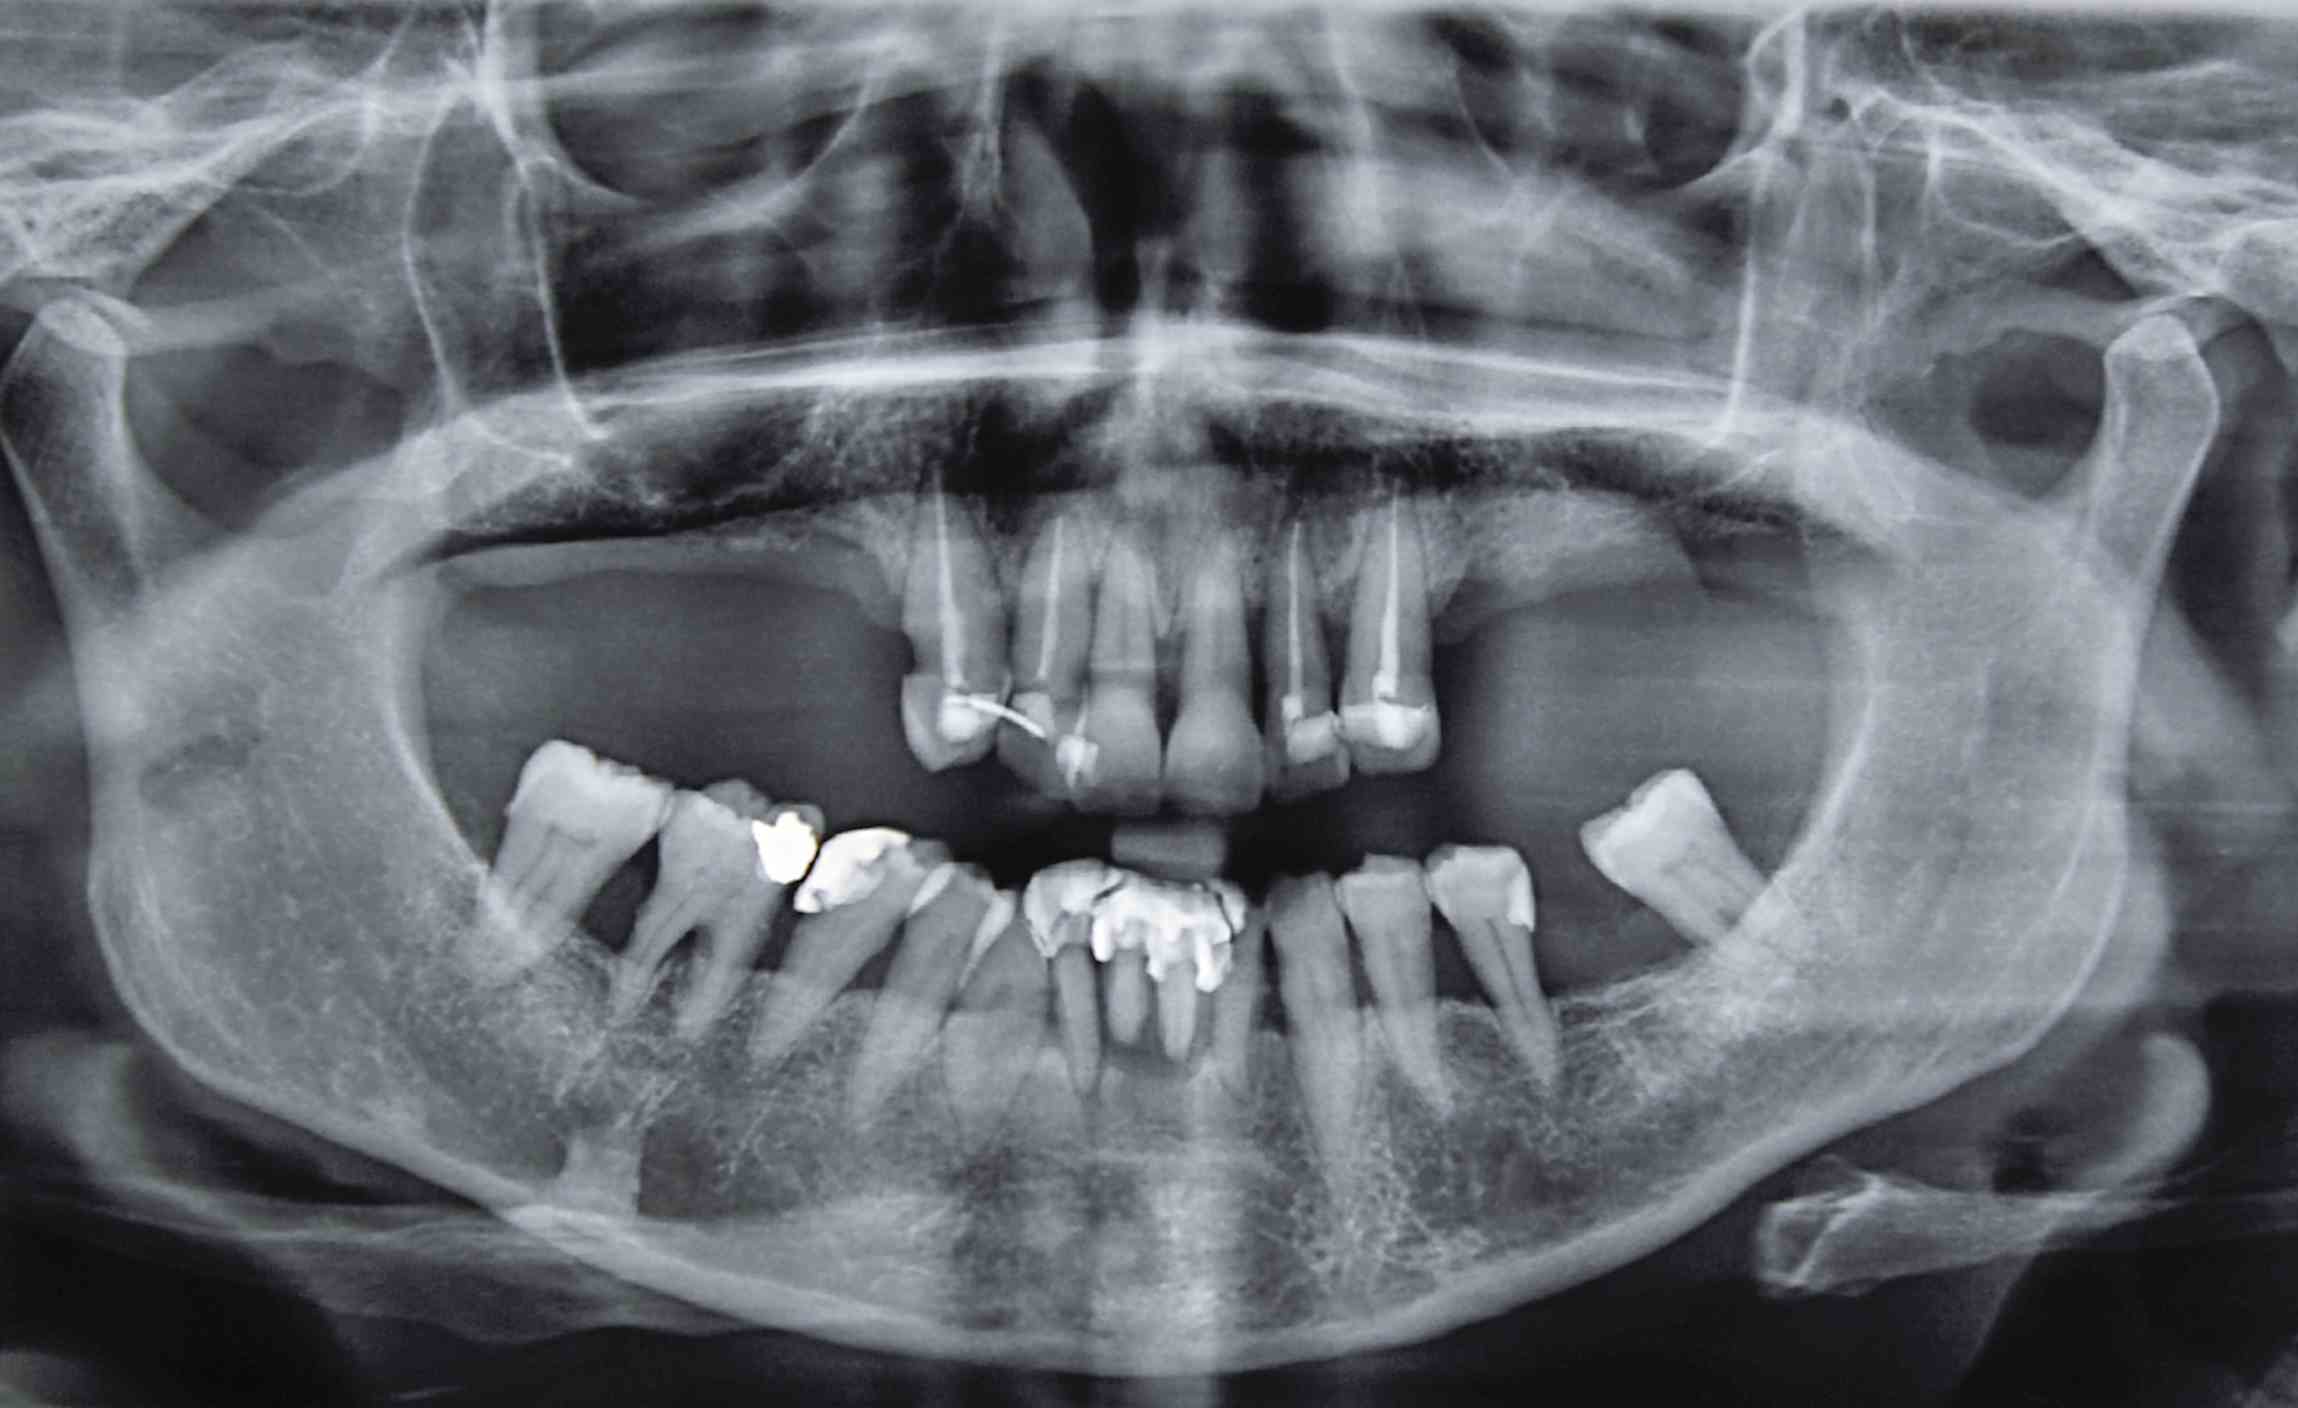

Оптг

1. Есть ли на снимке признаки воспаления в области верхушек корней зубов?

2. Наблюдаются ли ретенированные или дистопированные зубы?

3. Каково состояние костной ткани вокруг зубов — есть ли признаки резорбции или кисты?

4. Присутствуют ли патологические изменения в височно-нижнечелюстном суставе?

5. Поставьте  диагноз

6. Составьте  план лечения